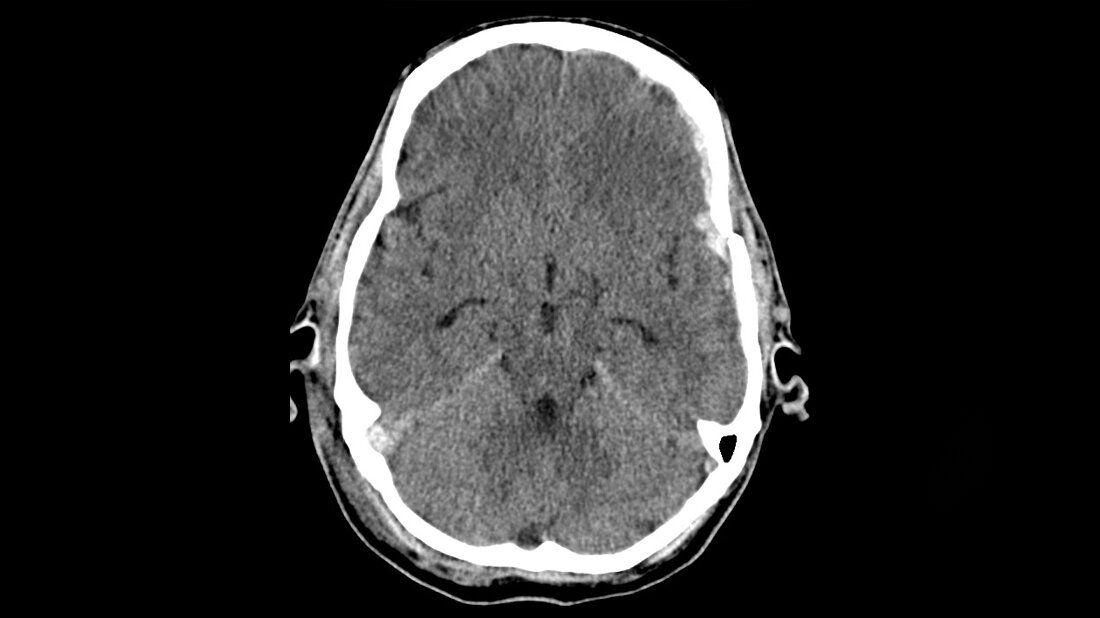

Titelbild zum Fachbeitrag zum Schädel-Hirn-Trauma in der Radiologischen Diagnostik

Coup-Contrecoup-Verletzung © D. Petersen